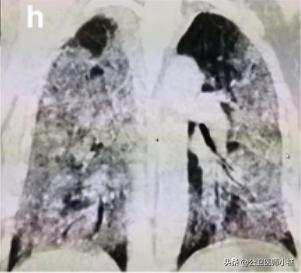

如果治疗不及时,或者免疫力无法抵抗病毒,则很可能威胁生命,发展为白肺。

白肺,肺部恶化

当然白肺在仅仅发生在极少数弥漫性肺部损伤且涉及多个肺叶的危重型患者。

在此阶段,患者肺通气功能严重受损需要持续性吸氧,甚至需要进行体外膜氧合(ECMO)俗称人工肺。